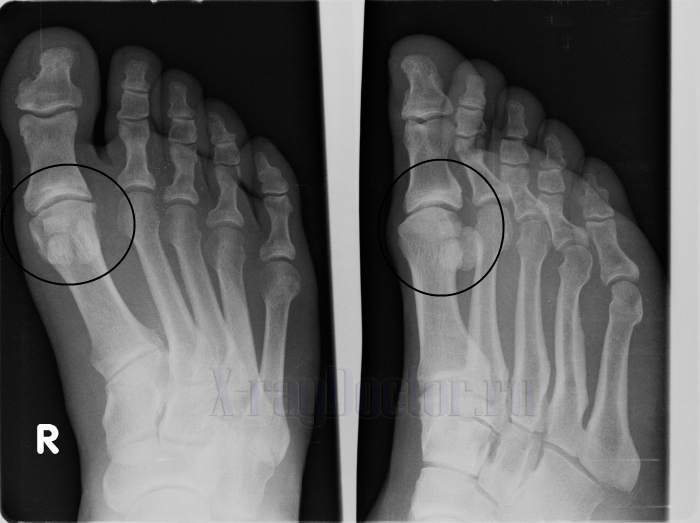

Остеосклероз суставов нижних конечностей

Наиболее болезненно у людей пожилого возраста протекает субхондральный склероз тазобедренного сустава. При такой форме заболевания велик риск перелома шейки бедра.

Если больной испытывает ноющую боль в области поясницы и тазовых костей, то, скорее всего, произошла деформация в области вертлужных поверхностей. Болевые ощущения могут возникнуть в области бедра, а это значит, что очаг заболевания располагается именно там.

На первых порах больной ощущает те же симптомы, что при субхондральном склерозе позвоночника. Однако через некоторое время в области тазобедренного сустава возникает нарушение движения, что позволяет сделать выводы об истинной локализации заболевания.

Об остеосклерозе коленного сустава можно говорить при наличии типичных щелчков во время движения. Происходит разволокнение связок, из-за чего появляется болевой синдром.

У больного затрудняется движение, он не способен сгибать колени, и вынужден либо хромать, либо ходить на «прямых» ногах. Пренебрежение своевременным лечением субхондрального склероза колена способно «посадить» человека в инвалидное кресло.